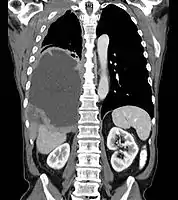

Mesothelioma Overview

- Malignant Mesothelioma